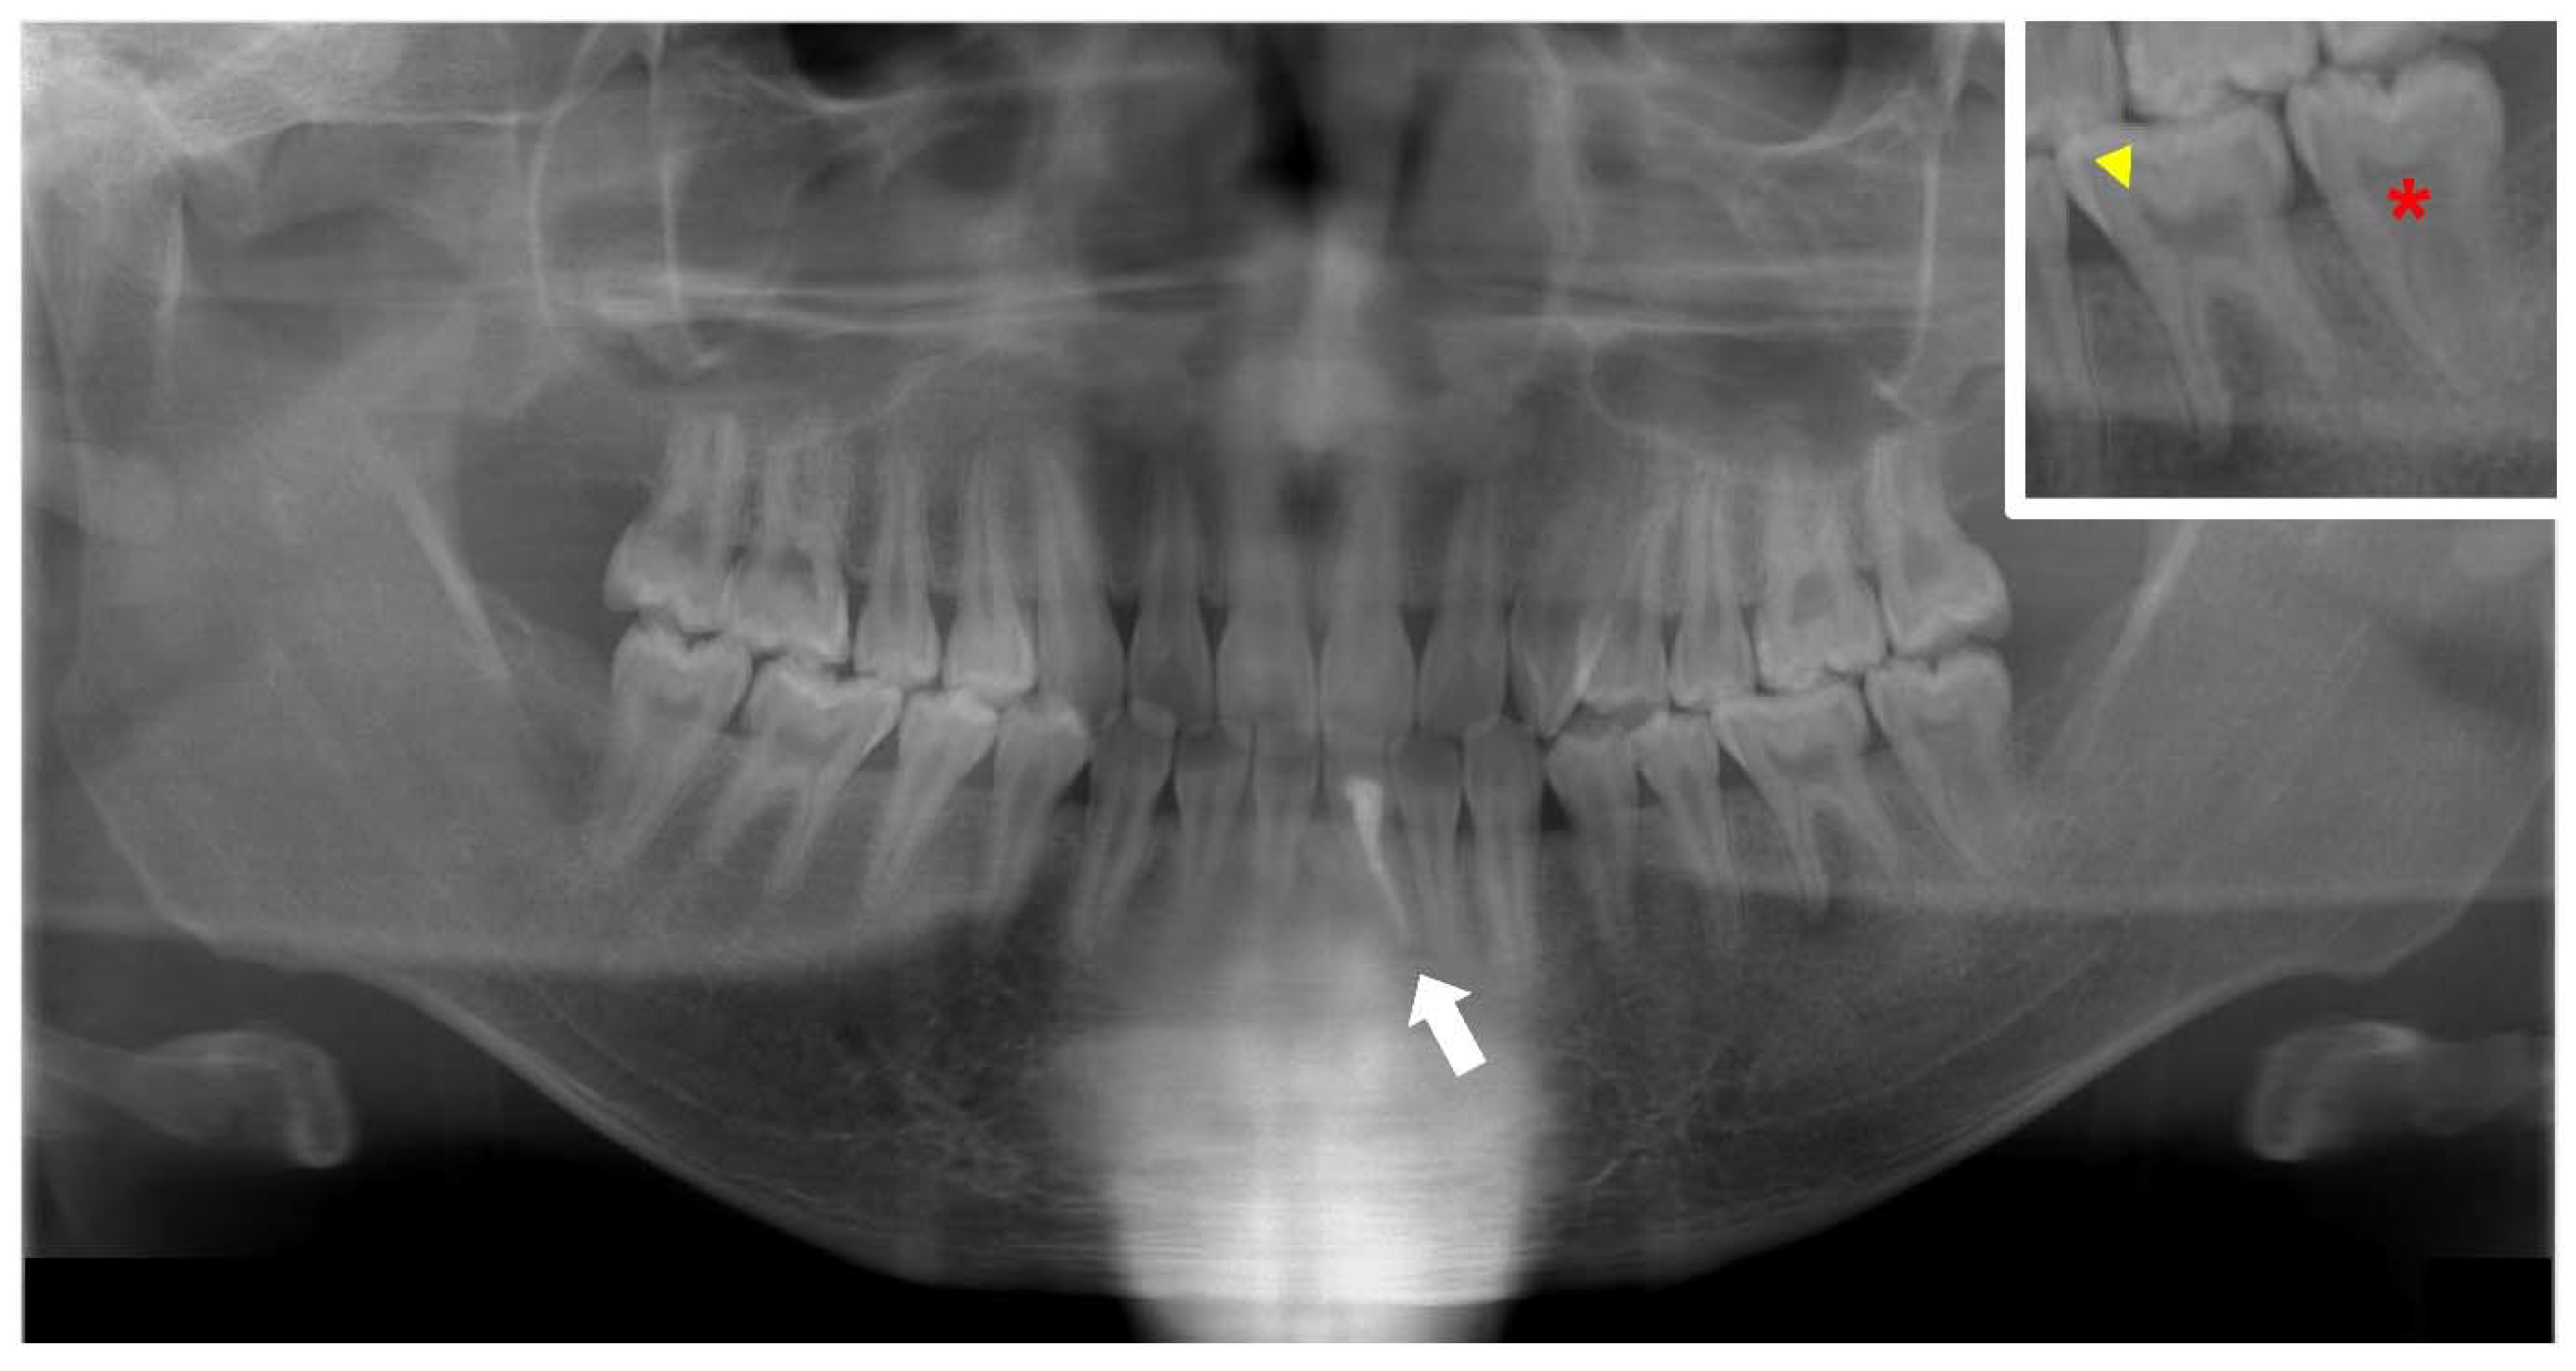

- Okawa, R.; Hamada, M.; Takagi, M.; Matayoshi, S.; Nakano, K. A Case of X-Linked Hypophosphatemic Rickets with Dentin Dysplasia in Mandibular Third Molars. Children 2022, 9, 1304. [Google Scholar] [CrossRef]